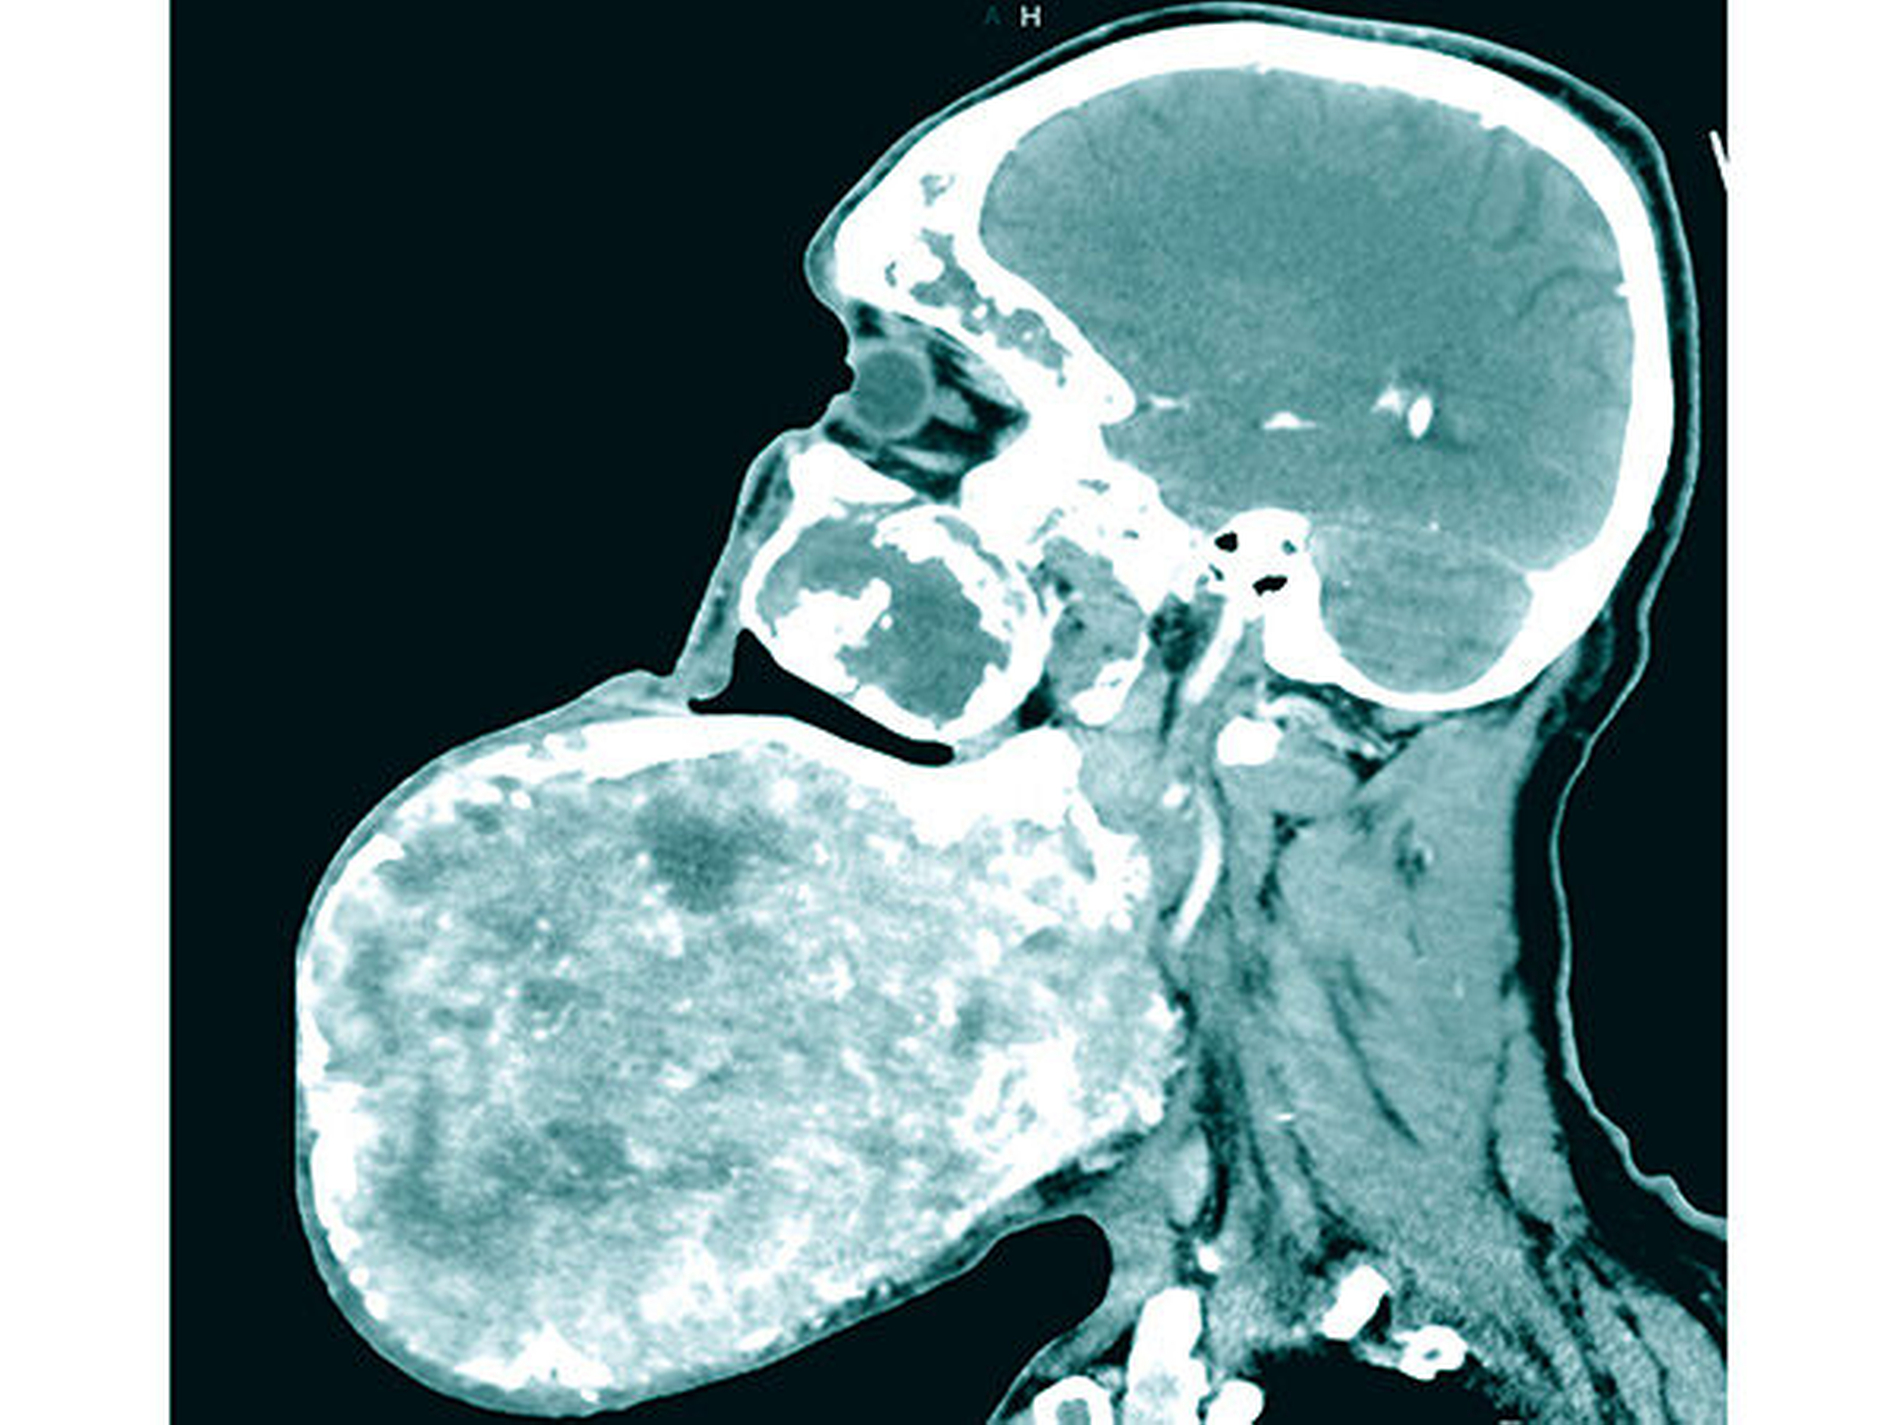

Klinisch zeigte sich eine circa 30 cm x 28 cm x 15 cm große, knochenharte und den Unterkiefer zu drei Vierteln umgreifende Raumforderung ohne Vincent-Symptomatik (Abbildung 1). In der Computertomografie zeigte sich eine inhomogene, blasige und hypodense Raumforderung mit Milchglasanteilen (Abbildung 2). Geplant wurde eine Abtragung der Veränderung mit Rekonturierung des Unterkiefers unter Verwendung eines statistischen 3-D-Formmodells, mit dessen Hilfe die ursprüngliche Form des Unterkiefers ermittelt wurde (Abbildung 3a). Im CAD/CAM-Verfahren wurden vier Resektionsschablonen hergestellt, um die geplante Osteotomie intraoperativ umzusetzen (Abbildung 3b).